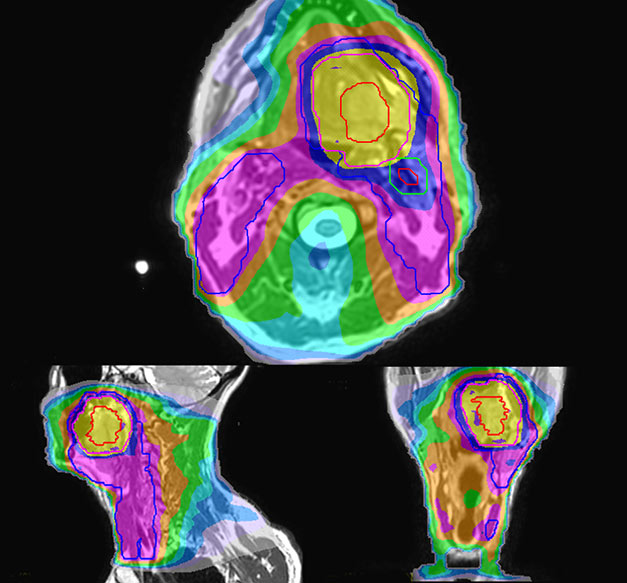

Personalized VMAT dose

Personalized VMAT dose planned in Philips Pinnacle.

MR-based contouring and planning

MR based target contouring

MR-based target contouring on 3D T2W TSE in transversal, sagittal

and coronal planes.